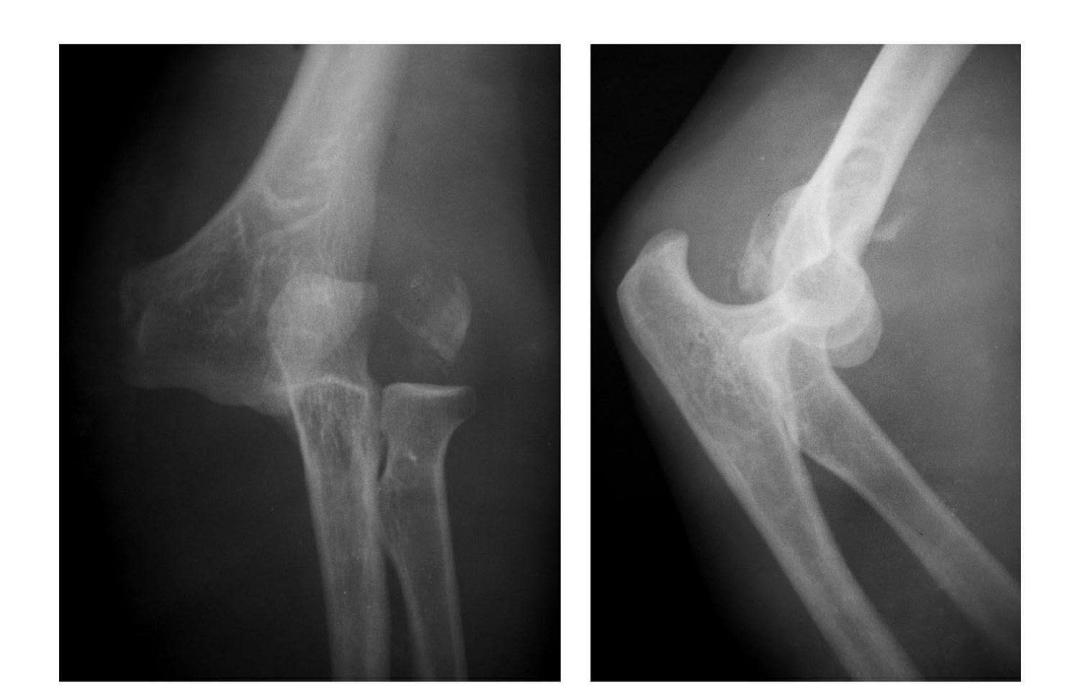

肱骨小头冠状面骨折

(一)完全骨折

本病亦称哈-斯(Hahn-Steinthal)型骨折

例1:肱骨小头基底部呈冠状面骨折,骨折块呈半球状向肘前上方移位。

例2:肱骨小头基底部冠状面骨折,骨折块呈半球状向肘前移位并肱骨内上髁无移位骨折。